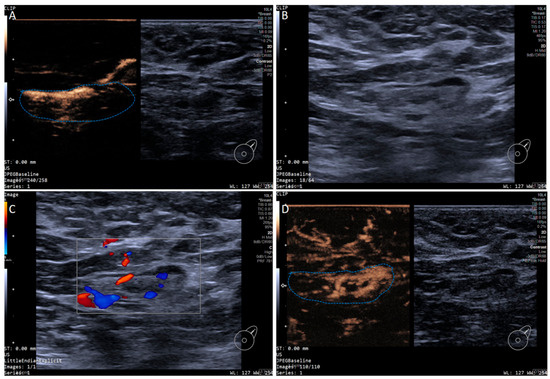

In addition, the SLN-IVCEUS enhancement patterns were divided into four types: type I showed homogeneous high enhancement; type II showed diffuse inhomogeneous high enhancement; type III showed no/low enhancement of the lymphatic hilus, homogeneous high enhancement of the cortex; type IV showed part of the cortical filling defect, low enhancement or high enhancement, the rest showed the performance of types I, II or III. And SLN-IVCEUS enhancement sequence was divided into three types based on the orders of bubbles entering the lymph nodes: centrifugal enhancement, centripetal enhancement, and diffuse enhancement. A malignant lymph node was diagnosed as long as one of the following conditions was met: (I) centripetal enhancement; (II) diffuse enhancement; (III) the enhancement mode of IVCEUS was type IV. SLN was diagnosed as malignant when PCEUS and/or IVCEUS diagnosed the SLN as malignant (Figure 2 and Figure 3).

Figure 3. Multimodal ultrasound imaging of pathologically confirmed metastatic sentinel lymph node. (A) Intradermal CEUS image (the enhancement pattern is type I, the blue dotted line delineates the contour of the SLN); (B) 2D US image; (C) CDFI image; (D) intravenous CEUS image (the enhancement pattern is II, the blue dotted line delineates the contour of the SLN).